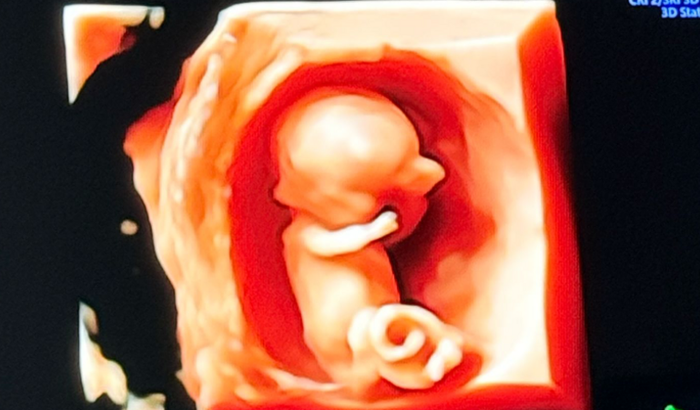

Recentemente, recebemos a notícia de que o Zay foi diagnosticado com gastrosquise, uma condição congênita rara em que parte do intestino e, às vezes, outros órgãos, se desenvolvem fora do abdômen por uma abertura na parede abdominal.

Essa condição exige cuidados médicos especializados e intervenções cirurgicas logo após o nascimento. Assim que o Zay nascer, ele vai precisar passar por uma cirurgia para reposicionar os órgãos dentro do abdômen e fechar a abertura. Esse processo é delicado e o tempo de recuperação pode variar, exigindo que ele fique internado na UTI Neonatal por semanas ou até meses.

Para aumentar as chances de sucesso do tratamento, o Zay precisa nascer até agosto, antes de completar as 38 semanas de gestação. Estamos nos preparando para oferecer a ele o melhor cuidado possível, mas os custos com exames frequentes, acompanhamento médico hospitalizado, cirurgias e a longa internação hospitalar são extremamente altos.